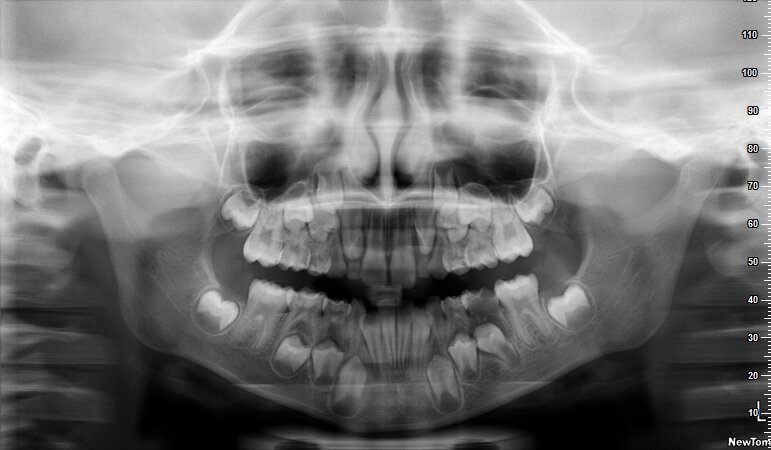

La piccola Sofia viene sottoposta a una prima visita ortodontica all’età di 8 anni, l’esame obiettivo (Figg. 1, 2) e l’ortopantomografia (Fig. 3) delle arcate dentarie evidenziano una mancanza di spazio per la corretta eruzione dei canini superiori (1.3-2.3).

Per motivi personali, i genitori di Sofia la sottopongono nuovamente alla nostra attenzione un anno dopo. Viene eseguita una nuova ortopantomografia (Fig. 4) che mostra un peggioramento del percorso eruttivo dei canini.

Fig. 3_Ortopantomografia iniziale.

Fig. 4_Ortopantomografia 1 anno dopo.